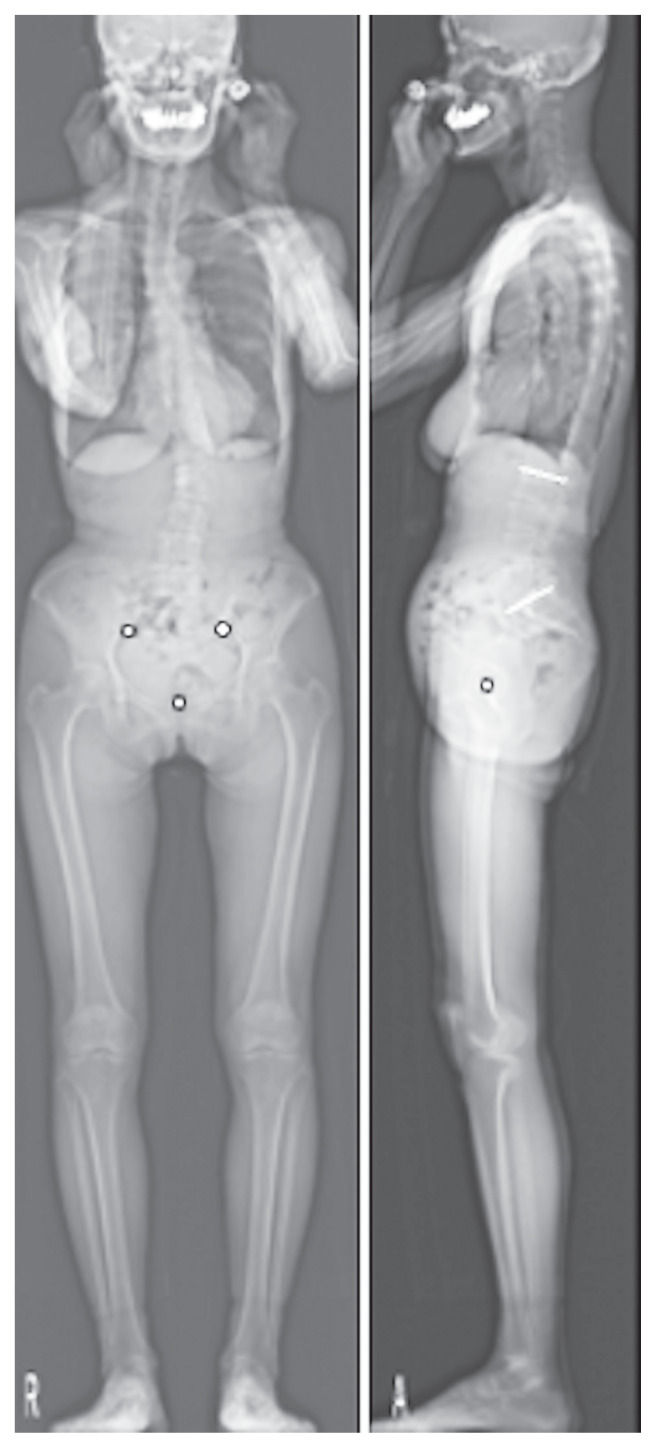

Purpose: To determine the effectiveness of the pelvic ring ratio as an indicator for assessing pelvic tilt (PT) from the frontal view and explore its correlation with various whole-body sagittal alignment (WBSA) parameters using EOS imaging technology.

Overview of literature: Traditional indicators of PT often rely on sagittal plane measurements, which can be challenging in cases of pelvic rotation or obesity. A new indicator such as the pelvic ring ratio could address these challenges and aid in the comprehensive assessment of pelvic alignment.

Methods: In total, 104 healthy participants (28 men, 76 women; mean age, 52.8±12.3 years) with no spinal disorders were recruited. Whole-body radiography using the EOS imaging system was performed to obtain sagittal and coronal parameters, including the pelvic ring ratio. Intra- and interobserver variability were assessed using intraclass correlation coefficients (ICCs) based on measurements by three spine surgery specialists. Correlation analyses among the pelvic ring ratio, age, body mass index, and WBSA parameters were conducted, and a multiple linear regression model was developed to predict PT.

Results: The mean pelvic ring ratio was 53.3%±11.5%. The intra- and interobserver ICCs were 0.89 and 0.87, respectively, indicating good reliability. The pelvic ring ratio was negatively correlated with age (r =-0.387, p <0.05) and PT (r =-0.598, p <0.05). The regression model revealed that the pelvic ring ratio and sex significantly predicted PT (p <0.05). Women had higher pelvic ring ratio (55.0%±11.3%) than men (48.6%±10.8%).

Conclusions: The pelvic ring ratio is a reliable and valuable indicator for PT assessment from the frontal view. It exhibits significant correlations with age and certain WBSA parameters, showing potential to improving the diagnostic accuracy and treatment planning for patients with spinal and hip disorders.